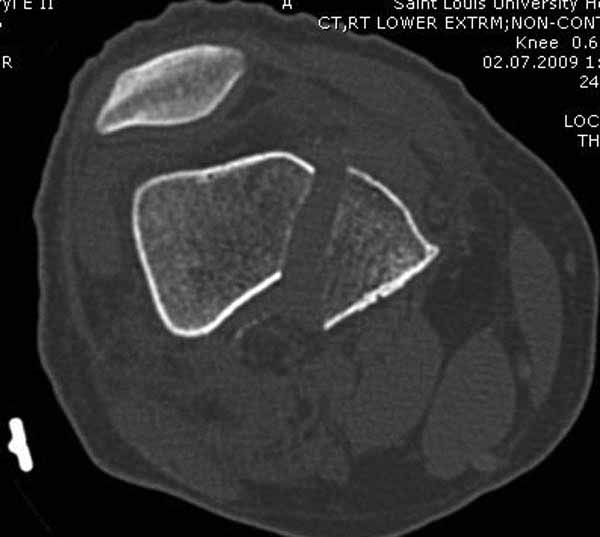

Однако в случае, представленном Константином Никитиным, не может быть применён ни ретроградный ни антеградный остеосинтез. Причина - нереально выполнить вышеуказанные необходимые требования, касающиеся дистальных блокирующих винтов. Из-за низкого перелома латерального мыщелка (перелом Hoffa) невозможно через него провести хотя бы 2 блокирующих винта, поскольку линия перелома мыщелка расположена либо на уровне верхушки межмыщелковой ямки либо незначительно проксимальнее. Поэтому авторам, с моей точки зрения, необходимо прислушаться к рекомендациям Джолдаса.

Рационально ориентироваться на качественный аспект - проблема или решается, или нет. Переломы типа 33C1 или C2 (то есть без фронтального раскалывания мыщелков, как на показанной Вами томограмме) при обычном качестве кости успешно можно фиксировать гвоздями с фронтальными винтами. Получается, их прочностных характеристик уже достаточно.